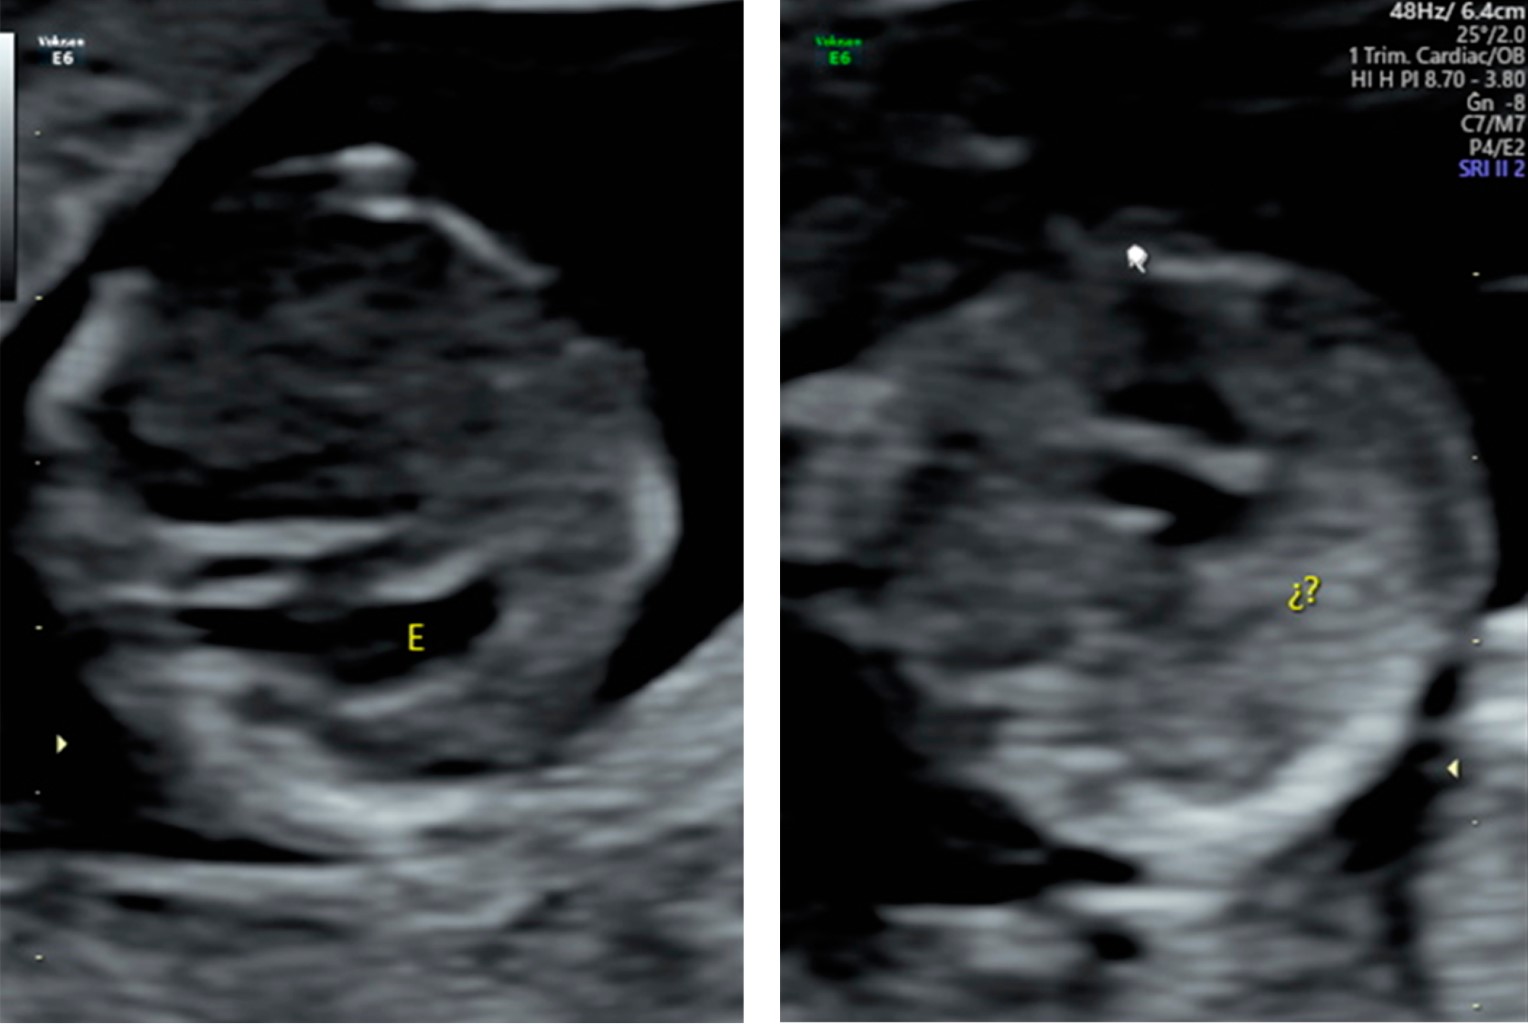

El síndrome de heterotaxia proviene del vocablo griego heteros (diferente) y taxis (configuración), se caracteriza por una configuración anormal en el eje derecho/izquierdo de los órganos torácicos y abdominales, los cuales se desarrollan en imagen en espejo "isómero" (Figuras 1 y 2).

Figura 1

Figura 2